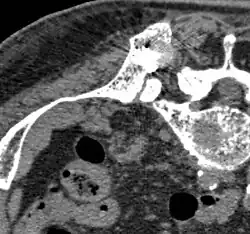

CT einer Prostatakrebs-Metastase im linken Schambein (im Bild rechts) -

Cholin-PET derselben Metastase im Schambein -

Fusionsbild aus CT und Cholin-PET der Prostatakrebs-Metastase im linken Schambein